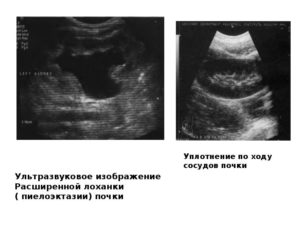

При получении результатов УЗИ многие пациенты видят такое заключение, как уплотнение чашечно-лоханочной системы (ЧЛС) обеих почек. Сразу отметим, что признаки уплотнения ЧЛС в обеих почках не несут угрозу здоровью. Это всего лишь термин ультразвуковой диагностики. Он означает, что ткань имеет повышенную плотность, поэтому волны пропускает не так хорошо.

Стенки ЧЛС могут стать плотнее в силу самых разных причин. Но чаще всего речь идет о хроническом пиелонефрите. Сонолог непременно заметит, что пораженная почка уменьшилась в размере.Также на мониторе будет видно, что ее контуры неоднородны. Чашечки и лоханки будут деформированы. Их края выглядят неровными. Такая картина может наблюдаться и при мочекаменной болезни, рефлюксе, каликоэктазии.

Поэтому заключение ультразвуковой диагностики не является диагнозом. Это просто констатация факта о том, что есть уплотнение ЧЛС почек.

Все органы, имеющие паренхиму, могут выглядеть на УЗИ более плотными при наличии каких-то патологий. Зачастую это признак воспаления. В такой период изменяются сосуды — венулы и капилляры, которые являются частью микроциркуляторного русла. Сюда же можно отнести и изменения соединительной ткани. Она реагирует на местного раздражителя — болезнетворного агента.